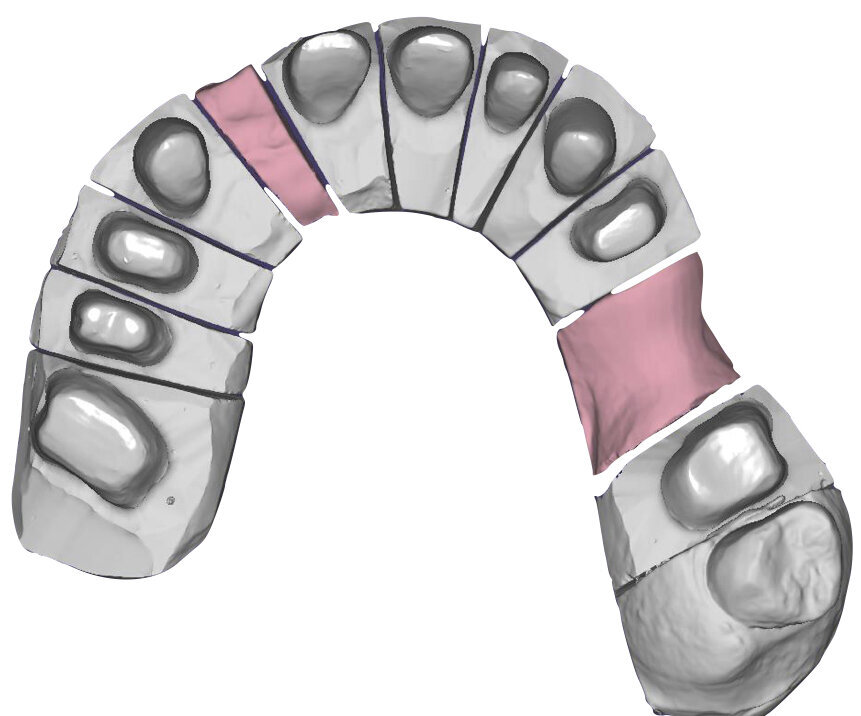

Il fresato ottenuto è poi riportato su articolatore Reference SL – già opportunamente programmato – e viene dall’Odontotecnico competente più precisamente funzionalizzato secondo i criteri della programmazione funzionale sequenziale, evidenziando con cere colorate i rapporti di centrica, le funzioni di mediotrusiva e protrusiva e le protezioni retrusive. I monconi sfilabili consentono la modellazione della sequenzialità mediotrusiva con la guida incisale indicata dalla registrazione axiografica (blu) (Figg. 34-37). La ceratura sequenziale è ora scansita con Sirona InEos X5 su Exocad, ed il modellato viene ricontrollato al CAD per spessori, connessioni e morfologia, e nella regolazione degli offsets per la ripreparazione dei monconi, ed è inviato al CAM per la fresatura dei II provvisori in Bredent breCAM.multicom, un PMMA con microriempitivo ceramico ad alta stabilità, su Dental Plus 5 Axis Milling Machine. La rifinitura dei monconi è seguita da ribasatura dei II provvisori in TRP - previo isolamento di tutte le superfici funzionali - e gli stessi sono poi rifiniti e lucidati. I soli elementi 3.3, 4.2 e 4.3 sono rimodellati in regione incisale con addictions in composito, secondo la morfologia studiata in ceratura. La consegna conferma la buona integrazione dei manufatti dal punto di vista estetico, occlusale, articolare e neuromuscolare, con controllo occlusale conforme al progetto (Figg. 38-42).

Il paziente utilizza questi secondi provvisori per otto settimane, durante le quali conferma la buona integrazione dei restauri e la soddisfacente funzione occlusale. Ciò è verificato con l’esecuzione di una nuova axiografia elettronica che già a due settimane dalla consegna evidenzia una buona risposta muscolare al nuovo design occlusale ed alla nuova postura mandibolare in TRP (Figg. 43-46). Provvediamo infine alle impronte per la costruzione dei manufatti definitivi in Zirconia-ceramica. I modelli sono scansiti in laboratorio con inEos X5 (Dentsply Sirona) su exocad (Figg. 47-49), ed una seconda scansione viene eseguita con i provvisori del Paziente posizionati sui modelli (Figg. 50-52). Il CAD consente di eseguire un matching fra le due scansioni, per cui i secondi provvisori utilizzati in TRP, con funzione occlusale sequenziale già completamente programmata, sono utilizzati per definire le morfologie dentali definitive di tutti gli elementi da restaurare (Figg. 53, 54) secondo il rapporto intermascellare definito (Figg. 55-58). Si esegue quindi fresatura al CAM della protesi definitiva in zirconia (Figg. 59, 60), la stratificazione e finitura ed infine la consegna al Paziente con cementazione in Panavia V5 (Figg. 61-65).